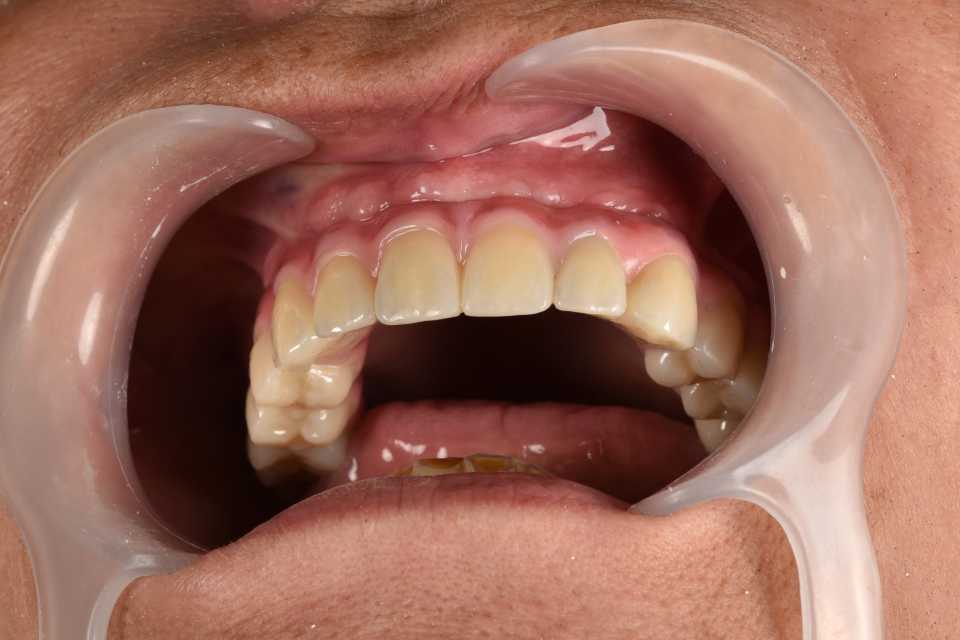

All on 6 cu implanturi orale speciale pterigoide, lucrare protezată din zirconiu pe suport de titan înșurubabilă

All on 6 cu implanturi orale speciale pterigoide, lucrare protezată din zirconiu pe suport de titan înșurubabilă.

Imaginile sunt prezentate în ordinea evoluției tratamentului, de la situația inițială la rezultatul final.